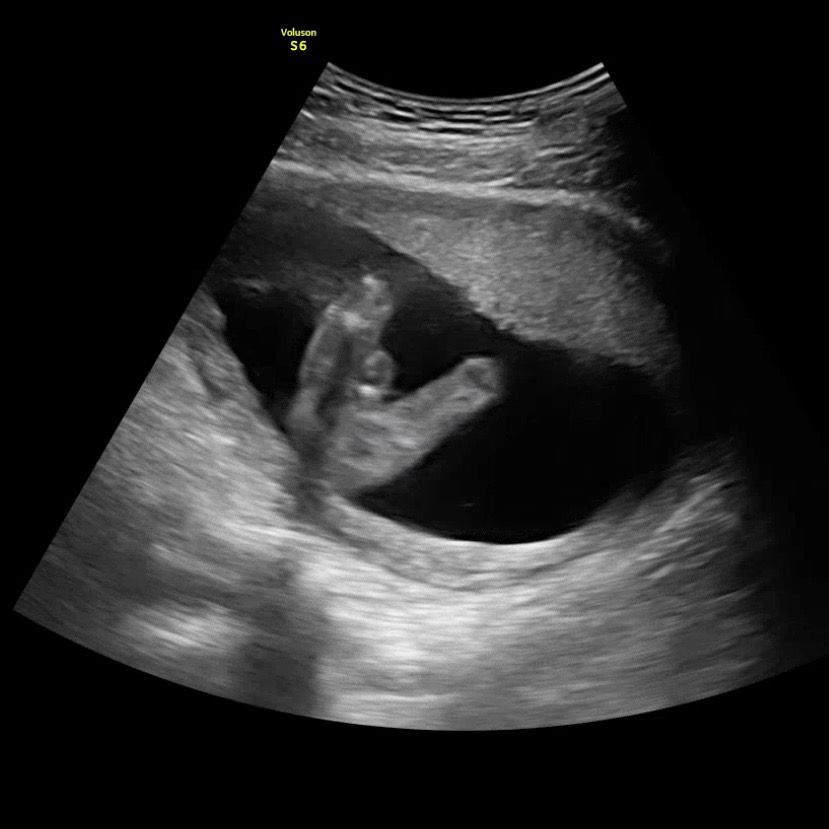

15주4일차 아들인지 확인부탁드려요

보이는게 있다고 하셨는데 저게 🌶️인가요?! 아직 16주가 안되서 긴가민가한 상태인데 아들인지 아닌지 궁금하네요~!

저는 미사일처럼 딱보이긴했는데 뭉툭해보여서ㅋ잘모르겠네요ㅋ